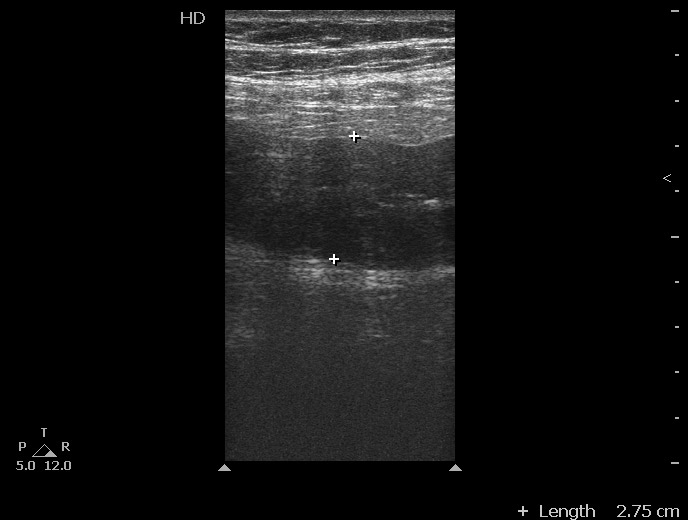

Молодая женщина, 36 лет.

Три дня назад поступила с жалобами на боли в животе в эпигастральной области. При УЗИ в БП небольшое количество жидкости - в малом тазу.

Аппендицит клинически исключен.

Повторный осмотр в связи с усилением болей в животе, появлением инфильтрата в эпигастральной области, снижением гемоглобина.

При УЗИ патологии печени, ЖП, панкреас, селезенки, почек не выявлено, имеется примерно прежнее количество свободной жидкости плюс изменения тонкой кишки:

При операции выявлен сегментарный тромбоз вен брыжейки тонкой кишки с некрозом петель.